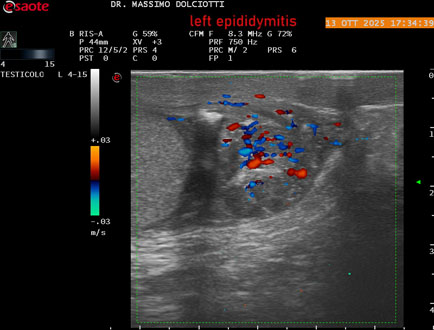

Data inserimento: 14/10/2025

Ecografia del: 13/10/2025

Strumento: Esaote MyLab Eight

Sonda: Lineare Multifrequenza 4-15 MHz

Età Paziente: M 70 anni

Motivazione dell'esame: da 2 giorni dolore al testicolo sinistro.

Commento all'esame: le immagini ed il video documentano l'epididimo sinistro spiccatamente aumentato di volume e di vascolarizzazione, come da flogosi. Didimo sinistro lievemente aumentato di volume. Quadro clinico ed ecografico da ricondurre ad epididimite acuta sinistra.

Conclusioni: epididimite acuta sinistra (acute left epididymitis).

Presentazione: Dr. Massimo Dolciotti - Ancona

Elaborazione digitale: Andrea Dini - Ancona